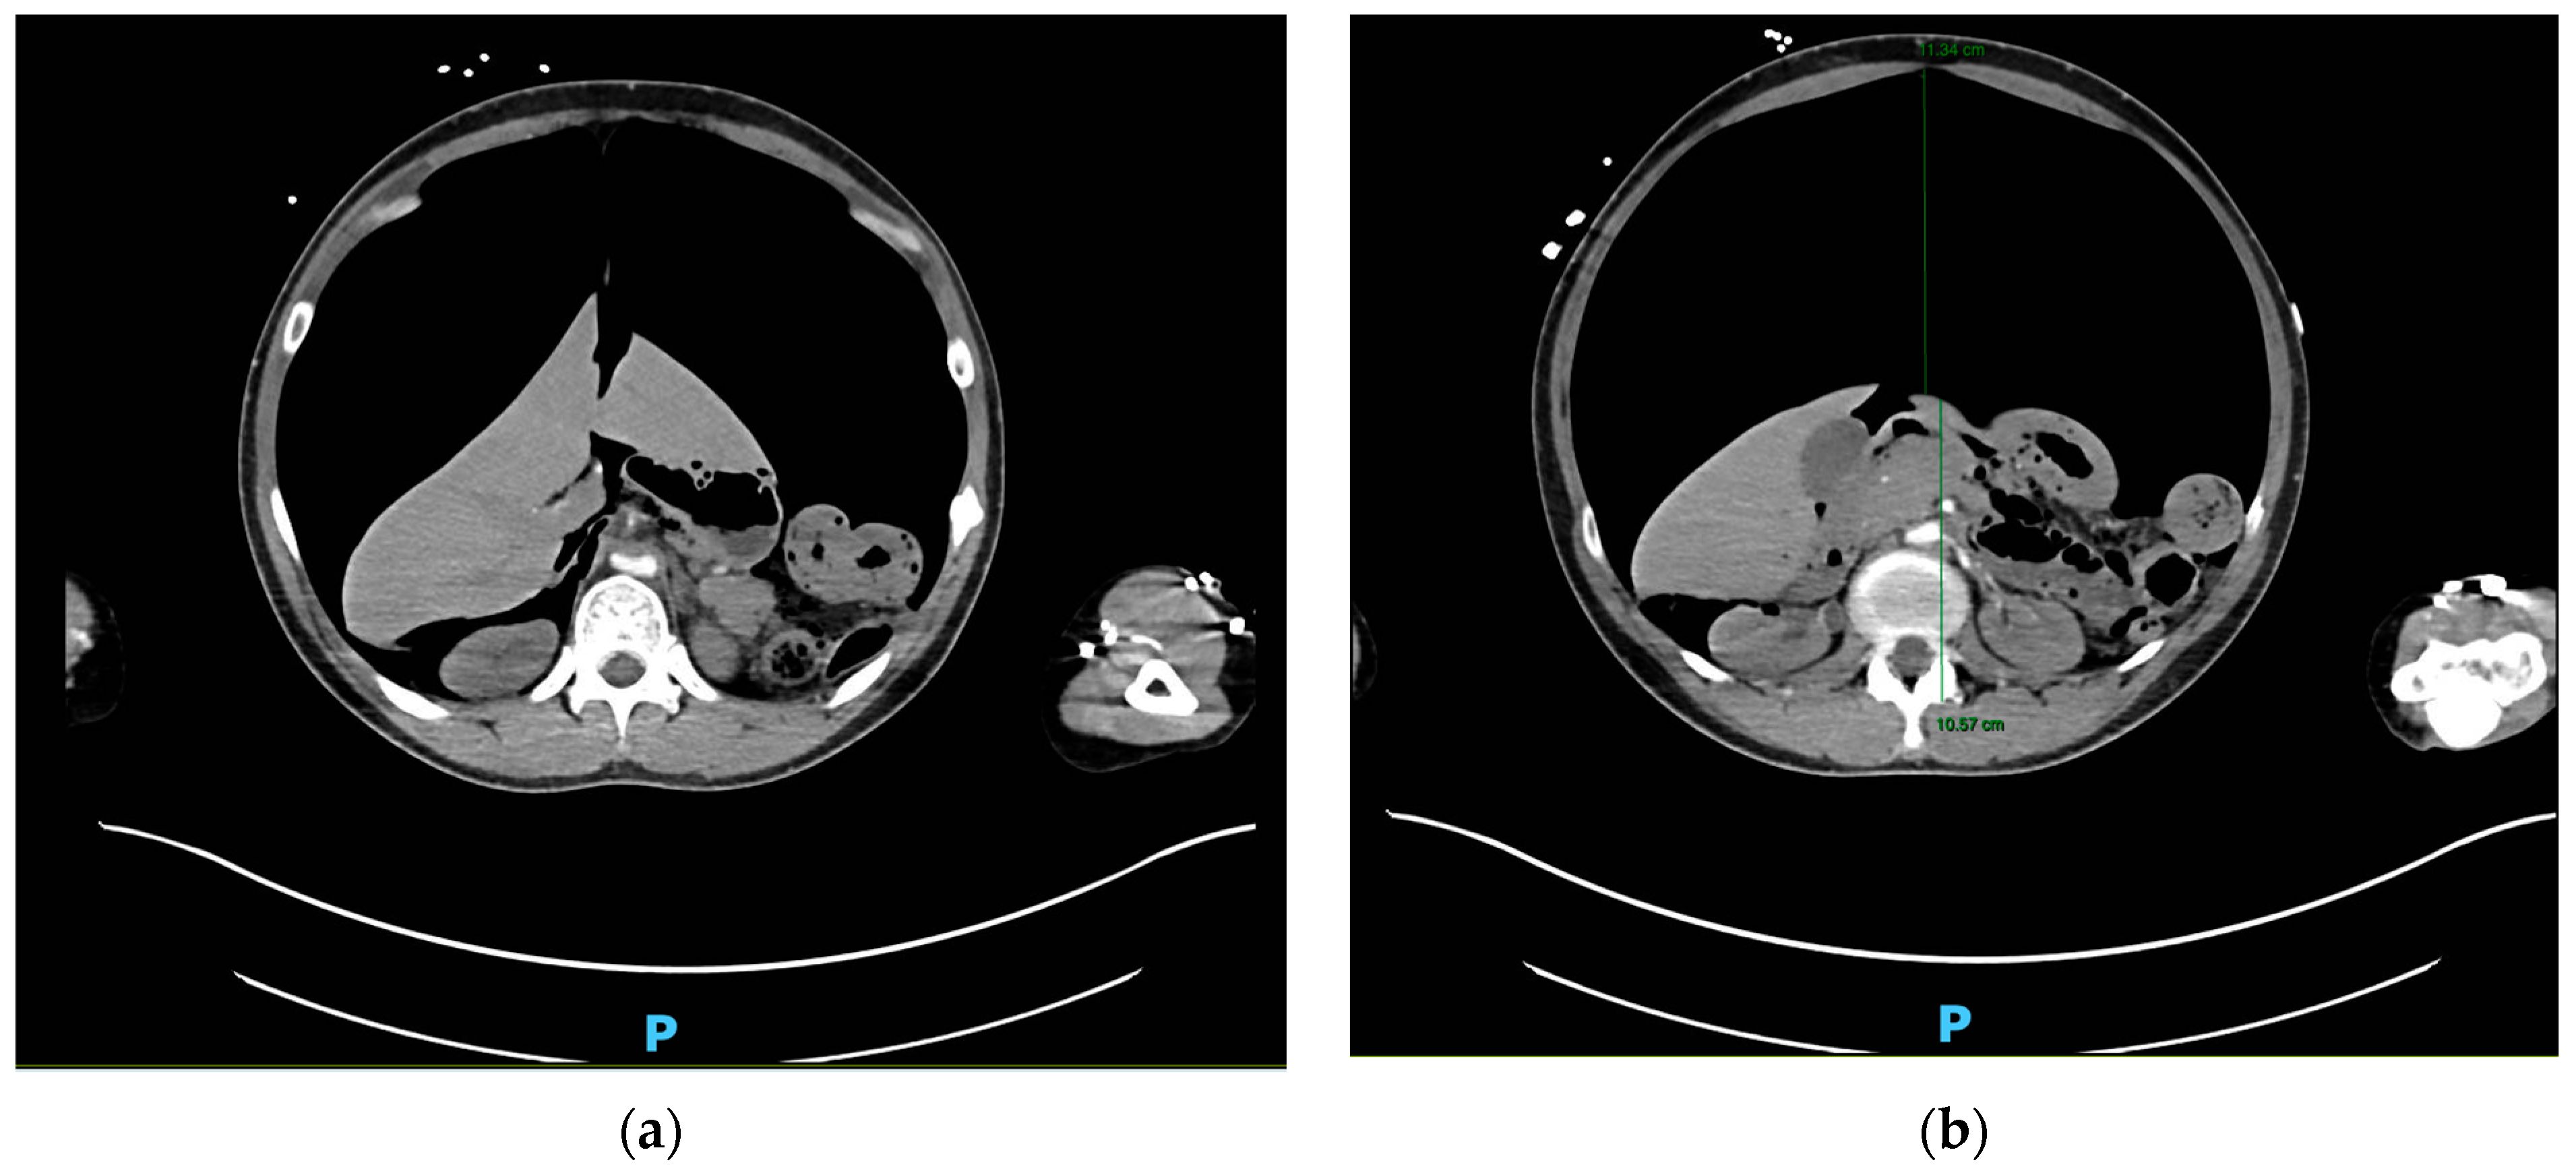

Gastric Perforation from Bag-Valve-Mask Ventilation Resulting in Tension Pneumoperitoneum and Arterial Insufficiency

2. Case Presentation